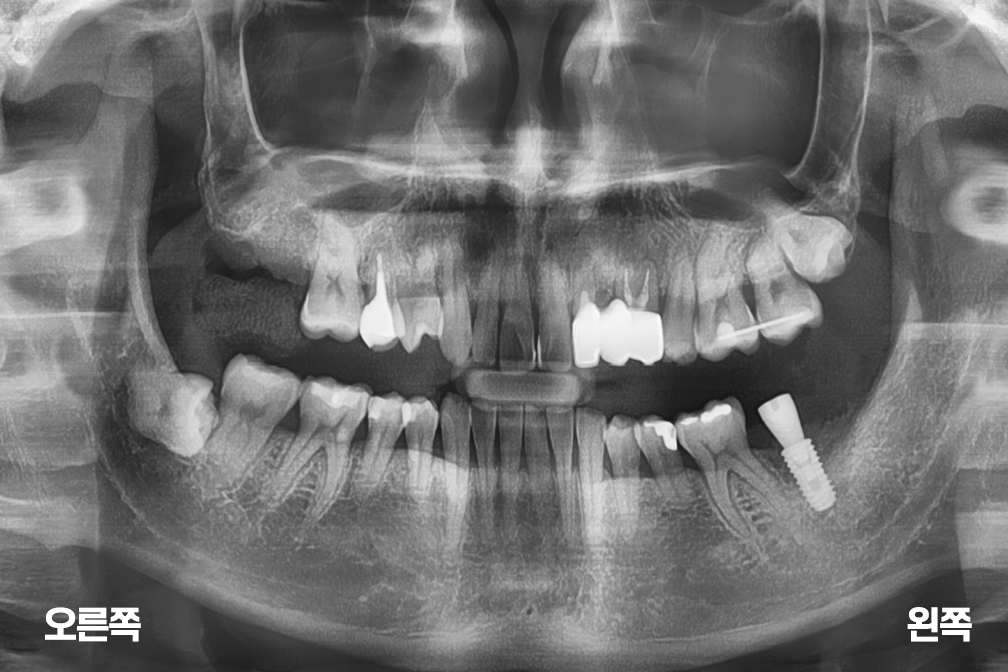

임플란트 오른쪽 윗 어금니 임플란트 및 왼쪽 아래 어금니 보철

After 2021년 9월 16일